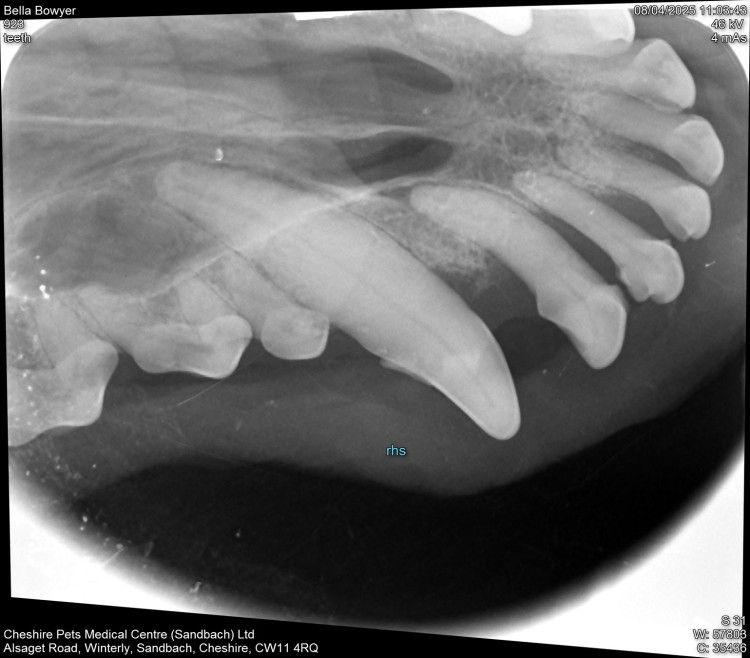

One pet owner with an 11 year old Cockapoo discovered the animal needed teeth extracting following her Pet Health Club examination.

"It can be upsetting finding out. I wish I had started brushing Bella's teeth when she we first got her. It's very important to get her to relax and let me brush her teeth. We have always fed her carrot and apples to help clean her teeth but that isn't enough," said the owner.